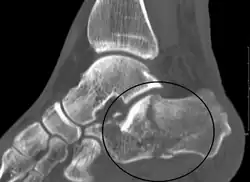

La radiographie standard est l'examen de première intention utilisé lorsqu'une fracture du calcanéus est suspectée. Les incidences recommandées sont : face, profil, dorsiflexion et rotation interne. Cependant, la visualisation de l'anatomie calcanéenne est limitée, notamment au niveau du ligament talo-calcanéen. Le scanner est actuellement la modalité d'imagerie de référence pour l'évaluation des lésions calcanéennes et a remplacé la radiographie standard dans la classification des fractures du calcanéus[11]. Les coupes axiales et frontales sont utilisées pour une bonne visualisation des ligaments de la base du pied.

L'angle de Gissane, ou angle critique, est l'angle formé par les parties descendante et montante de la face supérieure du calcanéus. Sur une radiographie de profil, un angle de Gissane supérieur à 130° suggère une fracture de la surface postérieure du ligament talo-calcanéen. L'angle de Böhler, quant à lui, est l'angle ouvert vers l'arrière et constitué par le croisement d'une ligne qui longe la face supérieure de la grande tubérosité du calcanéus et d'une autre ligne qui joint le point le plus haut du calcanéus et le point le plus haut de la grande apophyse du calcanéus. Un angle inférieur à 20° suggère un enfoncement de la facette postérieure et une possible fracture de l'os.